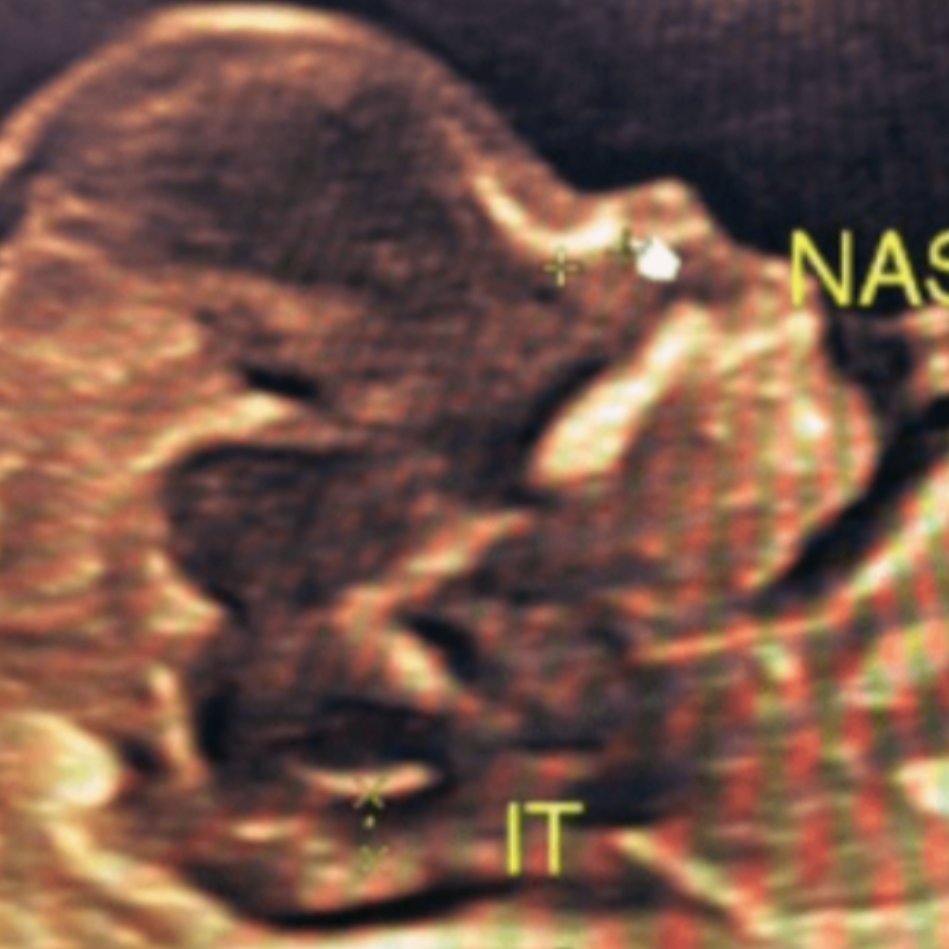

NTNB scan in rohini C-8/193 sector 8 rohini Delhi 110085, 7827070020, 9811552279 The NT/NB scan, also known as the nuchal translucency and nasal bone scan, is a prenatal ultrasound performed between 11 and 14 weeks of pregnancy. It assesses the risk of certain chromosomal abnormalities, specifically Down syndrome, Edwards syndrome, and Patau syndrome. The scan measures the fluid-filled space at the back of the baby's neck (nuchal translucency) and checks for the presence and development of the nasal bone. Here's a more detailed explanation: Purpose: The NT/NB scan screens for chromosomal abnormalities by measuring the nuchal translucency (NT) and evaluating the nasal bone (NB). Timing: It's typically performed between 11 and 14 weeks of pregnancy, as this is when the fetus is developed enough for accurate measurements. What it measures: NT (Nuchal Translucency): This measures the fluid-filled space at the back of the baby's neck. An increased NT measurement can indicate an elevated risk of chromosomal abnormalities. NB (Nasal Bone): This assesses the presence and development of the nasal bone. The absence or underdevelopment of the nasal bone can also be a marker for chromosomal abnormalities. Chromosomal Abnormalities: The scan helps assess the risk of conditions like Down syndrome (Trisomy 21), Edwards syndrome (Trisomy 18), and Patau syndrome (Trisomy 13). Screening Tool: It's important to note that the NT/NB scan is a screening test, not a diagnostic test. It provides information about the risk of these conditions but doesn't confirm a diagnosis.